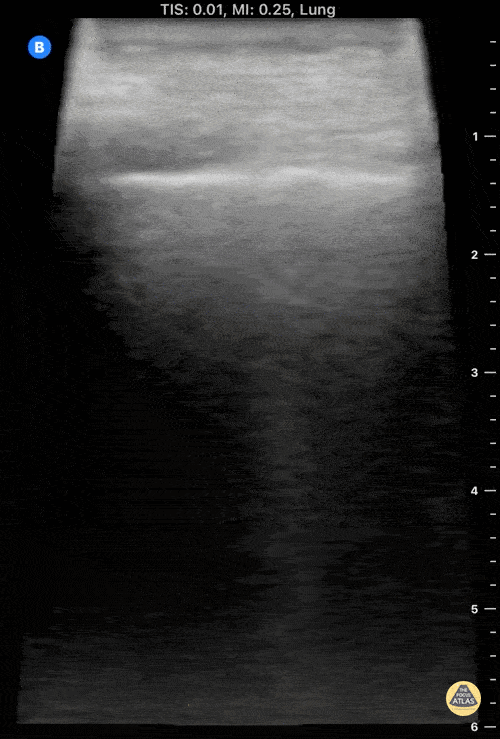

79 y/o patient with 1 week history of malaise, weakness, somnolence and loss of apetite. No cough or SOB, RX unremarkable. POCUS shows small sub-pleural consolidation in left lung base Dr Felipe Urriola P. Resuscitation Fellow The Royal London Hospital ED